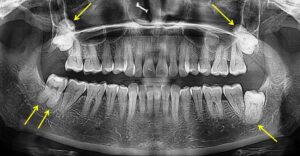

A 38-year-old female patient reported to a private dental clinic complaining of pain in the lower left back tooth region since past ten days. Patient was well nourished, moderately built with well behaviour. Patient did not show any history of past illness or signs and symptoms of systemic disorder, metabolic or syndromic diseases. There was no history of previous hospitalization or any orthodontic treatment taken in the past. Intraoral examination was performed which showed an erupting mandibular left third molar covered with inflamed peri-coronal flap. On contralateral side, the third molar was erupted and visible in the oral cavity. In the upper arch both right and left third molars were not erupted clinically. No other dental findings were observed apart from this. To confirm the presence of upper third molars and to see the condition of the lower left third molar a radiographic examination was carried out. On radiographic examination (orthopantomograph), mandibular left third molar was found with normal vertical position with insufficient space for its eruption (Figure 1). On further examination, it was found that roots of all third molars was bulky and bulbous with blunt root apices. The radiopacity was found all around the root encompassing entire length of the roots (Figure 1). This radiographic feature was not observed in other teeth. Finally based on the literature evidence and radiographic findings the case was diagnosed as localized idiopathic cemental hyperplasia or hypercementosis involving all four third molars. As patient’s chief complaint was associated with left lower third molar, a treatment plan consisting of surgical extraction of this particular tooth was made and patient was scheduled for the surgical extraction under local anaesthesia.

Figure 1: Orthopantomograph showing localized Cemental Hyperplasia or Hypercementosis involving roots of all four third molars (yellow arrows)